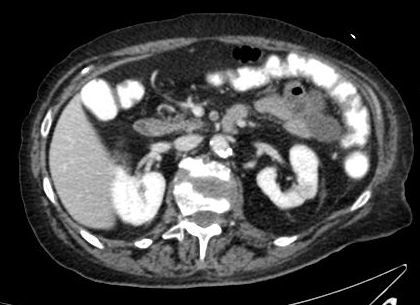

TDM hépatique injectée : que voit-on, quel est le diagnostic probable?

masse hépatique réhaussée au temps artériel, avec wash out au temps portal =\> CHC probable